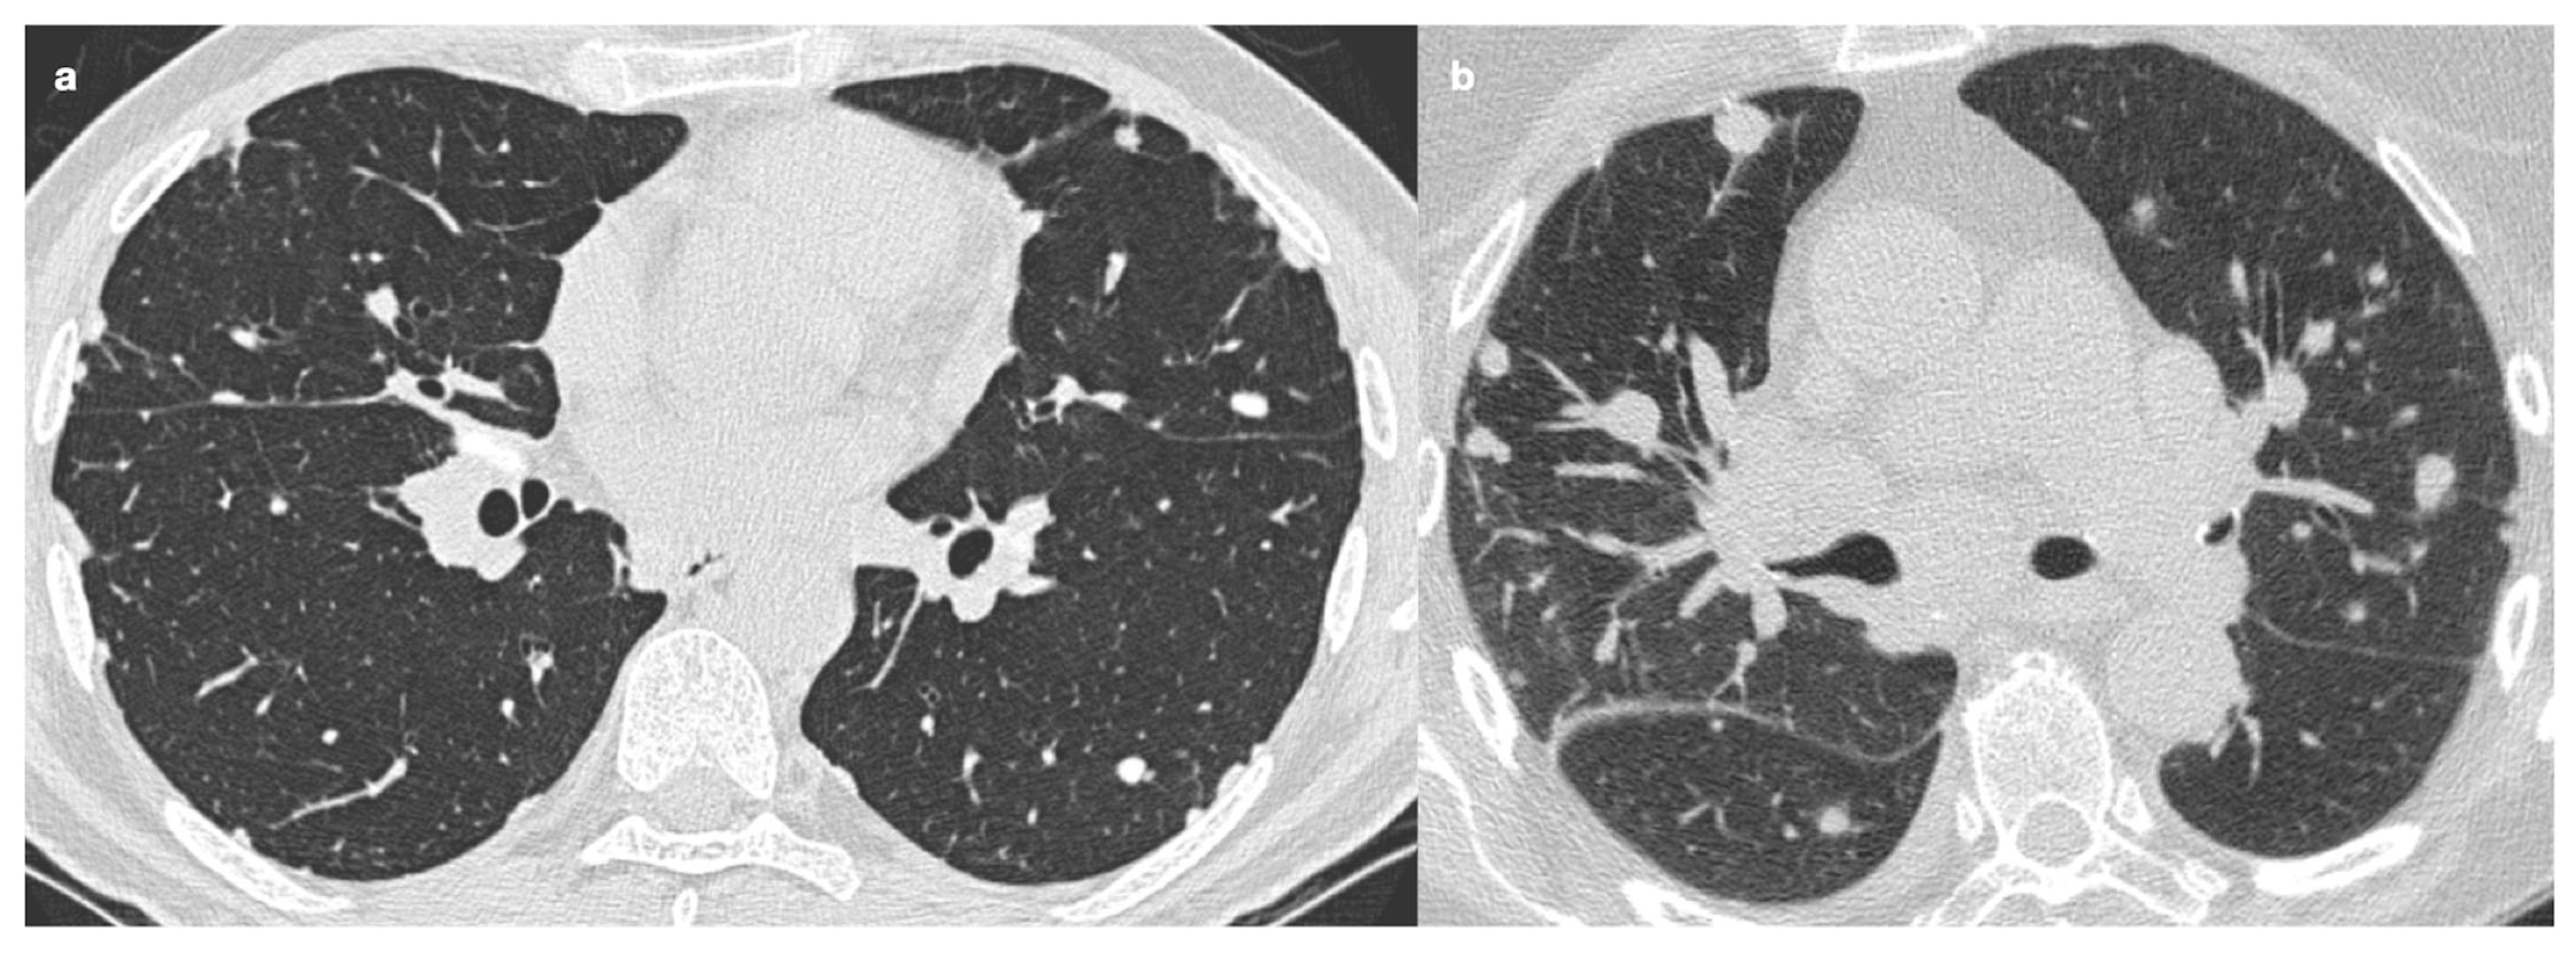

| Incidence | Approximately 20% of patients with sarcoidosis |

| Origin | Chronic inflammation, long-lasting disease, or phenotypic susceptibility |

| Alterations | Linear opacities, traction bronchiectasis, architectural distortion |

| Distribution | Predominantly in the upper lobes and peribronchovascular regions |

| Honeycombing | Present in about 10% of patients, typically localized in middle-upper lobes |